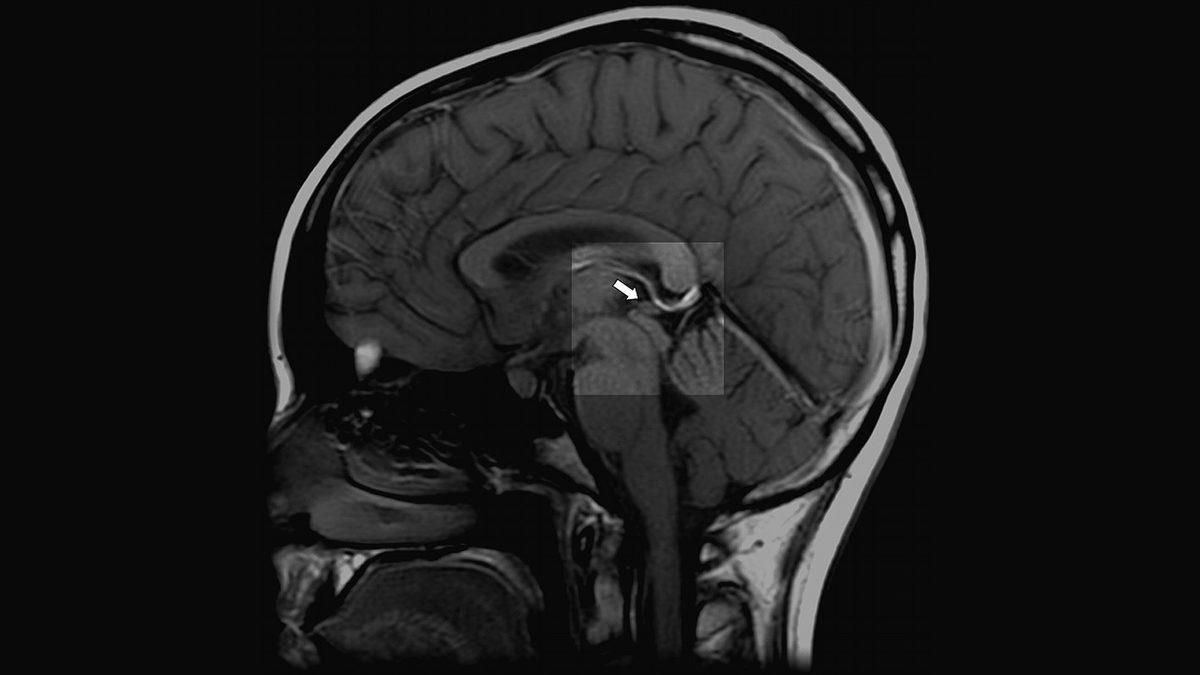

Epifiz bezi, beynin sağ ve sol loblarının birleşim noktasında bulunan epithalamus isimli bir alanın derinliklerinde bulunur. İngilizce adı pineal gland olan bu bölgenin adı, Latince çam kozalağı anlamında olan pinea kelimesinden gelmektedir. Çünkü eskiden bu bölgenin çam kozalağı boyutunda olduğu düşünülürdü ancak son yapılan çalışmalar bu bölgenin yalnızca bir bezelye kadar olduğunu ortaya koyuyor.

Epifiz bezi, yüksek oranda kalsiyum içerir ve duyularımızı kontrol eden talamus bölgesinin hemen üzerinde yer alır. Epifiz bezi, beynim tam orta noktasıdır. Öyle ki radyologlar beyin görüntüsünün incelemesi sırasında bu beze bir nokta koyarak orta alanı tespit eder ve bu nokta üzerinden incelemeler yaparlar. Boşuna ‘ruhun tahtı’ dememişler. Ancak bu bezin asıl önemi salgıladığı hormon ve bu hormonun insan yaşamına etkileridir..